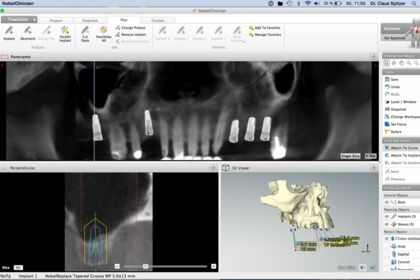

При сложном обширном лечении с коронками и имплантами, после изготовления трёхмерных рентгеновских снимков (DVT) с компьютерной томограммой мы симулируем сначала запланированное лечение.

В показанном ниже случае (мужчина 50 лет) мы заменили имплантами зубы, которые невозможно было больше сохранить, и обновили недостаточные коронки.